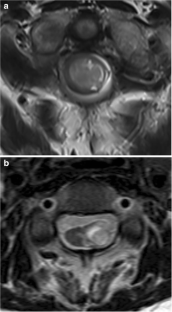

Diffuse midline glioma with histone H3 K27M mutation is a new entity described in the 2016 update of the World Health Organization Classification of Tumors of the Central Nervous System. The purpose of this study was to evaluate the clinical and imaging characteristics to predict the presence of H3 K27M mutation in spinal cord glioma using a machine learning–based classification model.

A total of 41 spinal cord glioma patients consisting of 24 H3 K27M mutants and 17 wild types were enrolled in this retrospective study. A total of 17 clinical and radiological features were evaluated. The random forest (RF) model was trained with the clinical and radiological features to predict the presence of H3 K27M mutation. The diagnostic ability of the RF model was evaluated using receiver operating characteristic (ROC) analysis. Area under the ROC curves (AUC) was calculated.

MR imaging features of spinal cord diffuse midline gliomas were heterogeneous. Hemorrhage was the only variable that was able to differentiate H3 K27M mutated tumors from wild-type tumors in univariate analysis (p = 0.033). RF classifier yielded 0.632 classification AUC (95% CI, 0.456–0.808), 63.4% accuracy, 45.8% sensitivity, and 88.2% specificity.

Our findings indicate that clinical and radiological features are associated with H3 K27M mutation status in spinal cord glioma.